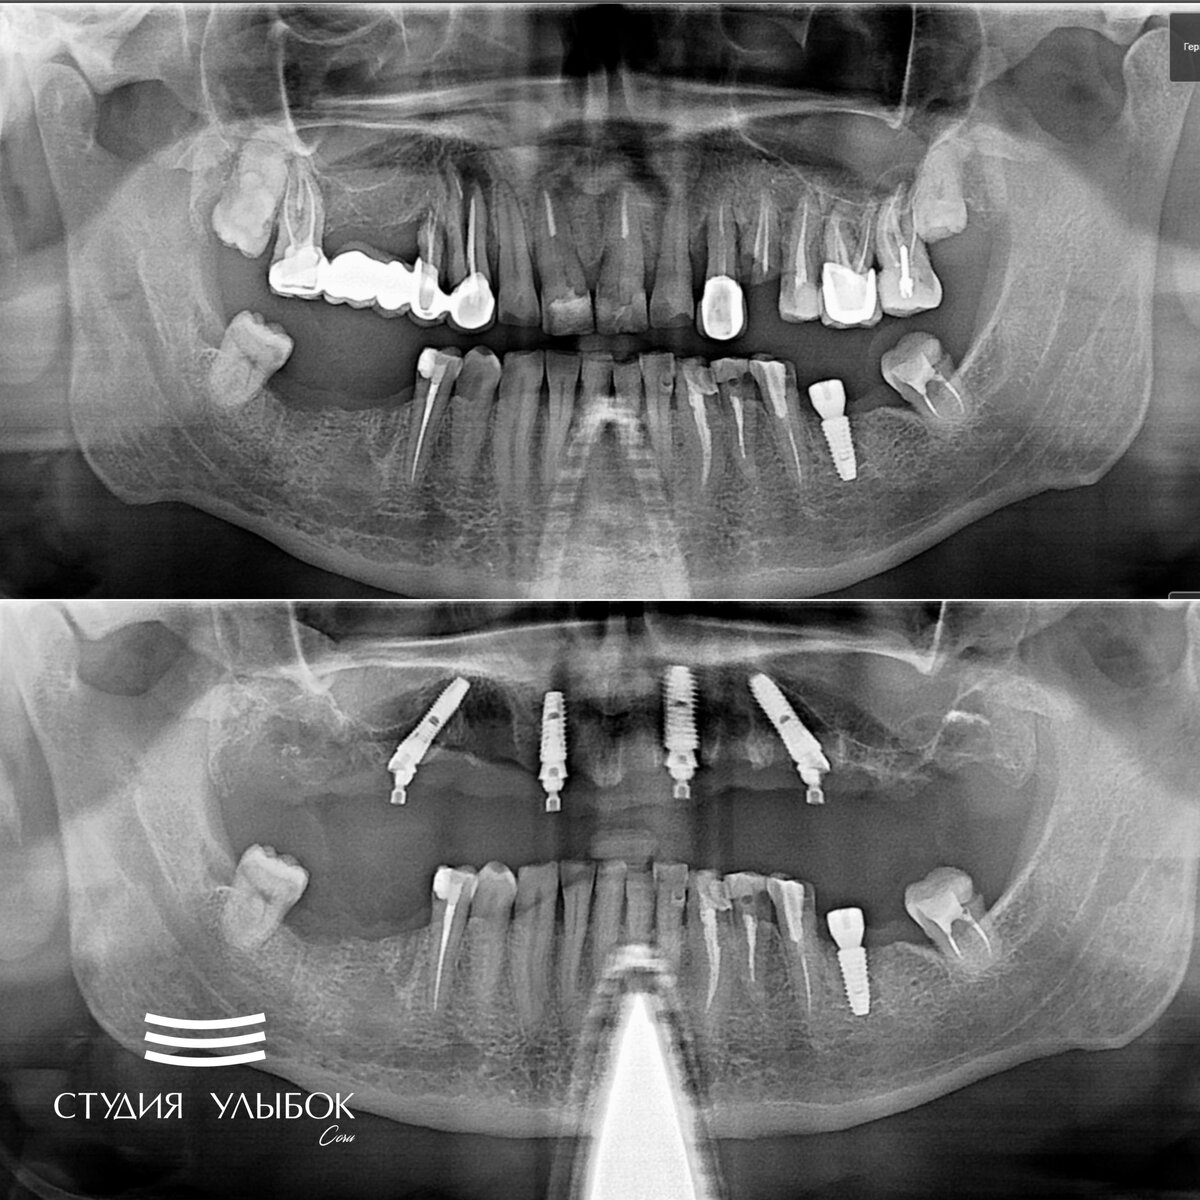

Сегодня кейс про пациента, который обратился с жалобой на ноющую боль в челюстях в процессе пережевывания пищи, а также на неприятный запах из ротовой полости. Помимо этого, эстетический вид зубов на верхней челюсти пациента абсолютно не устраивал.

После проведенного осмотра, тщательной и детальной диагностики клинической ситуации (КТ, ОПТГ) на рабочем врачебном консилиуме ортопедов и имплантологов было принято решение об удаление всех зубов и кист на верхней челюсти, и далее, установке имплантатов Dentium (Южная Корея) в технике «все на 4» (всё на четырех имплантатах).

Это означает, что на челюсть устанавливаются 4 имплантата под определенным углом, чтобы обеспечить устойчивость и надежность будущей ортопедической конструкции во рту. Далее, устанавливается временный протез до момента приживления всех имплантатов, и по истечение 6-ти месяцев, уже устанавливается постоянный условно-съемный протез. Название «условной-съемный», обозначает, что его может снять только врач на профилактическом приеме. В жизни такой протез пациент не снимает, просто обеспечивает гигиену и правильное питание. Ощущение у пациента такие, как будто у него свои красивые и здоровые зубы.

К сожалению, зубы на верхней челюсти у данного пациента имеют большое количество локаций воспалений (кист), из-за чего происходит оголение кости челюсти. В такой ситуации сохранить или восстановить зубы не представляется возможным. Это абсолютно нерационально и непрофессионально.

В итоге операция была успешно проедена. Установили имплантаты Dentiym SuperLine производства Южная Корея в позицию зубов 16, 12, 22, 26.

Снимок челюсти до процедуры и после вы видите на своих экранах.